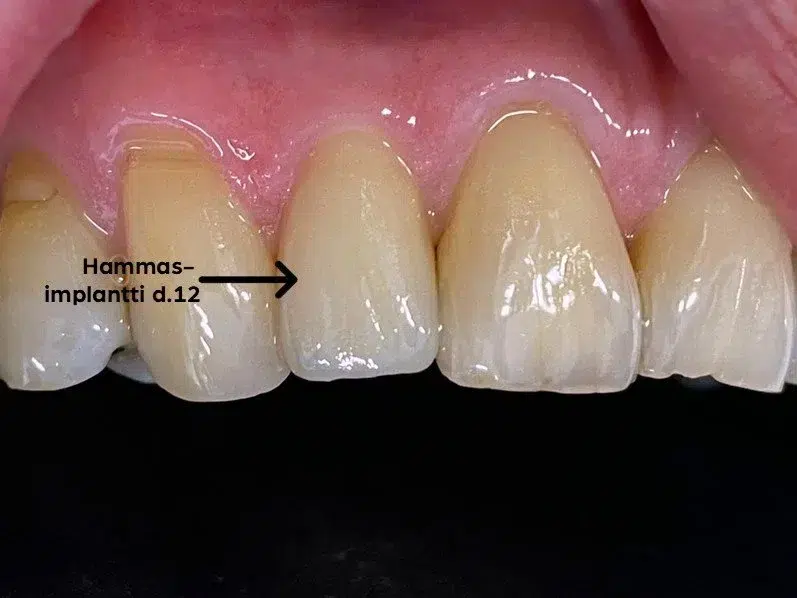

Immediaatti-implantointi lyhentää implanttihoidon kestoa, vähentää kirurgisten toimenpiteiden määrää ja parantaa estetiikkaa. Välittömässä implanttihoidossa keinojuuri ja väliaikainen hammaskruunu asetetaan hampaan poistokuoppaan heti hampaan poiston jälkeen, yhden vastaanottokäynnin aikana.

Ensimmäisen hoitokerran jälkeen implanttiruuville annetaan muutaman kuukauden mittainen luutumisaika, jonka jälkeen implanttiin päästään kiinnittämään pysyvä, useimmiten keraaminen hammaskruunu. Luutumisaika on yhtä pitkä kuin perinteisessä implanttihoidossa.

Kun implantointi tehdään immediaattina, hoito on tavanomaista nopeampi ja tuloksetkin usein tavallista esteettisempiä.